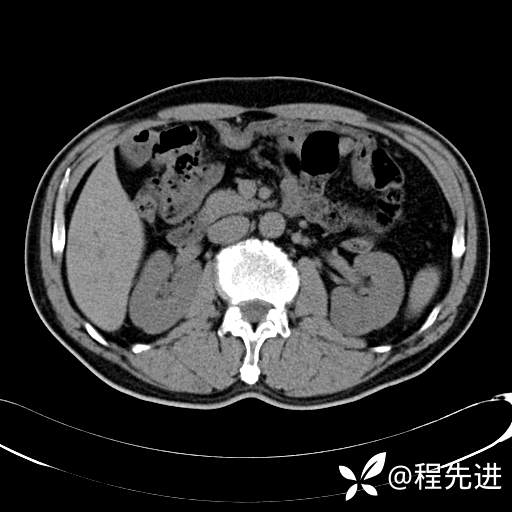

患者性别:男

患者年龄:65岁

简要病史:腰痛2月,体检发现左肾占位5天

髓质期: